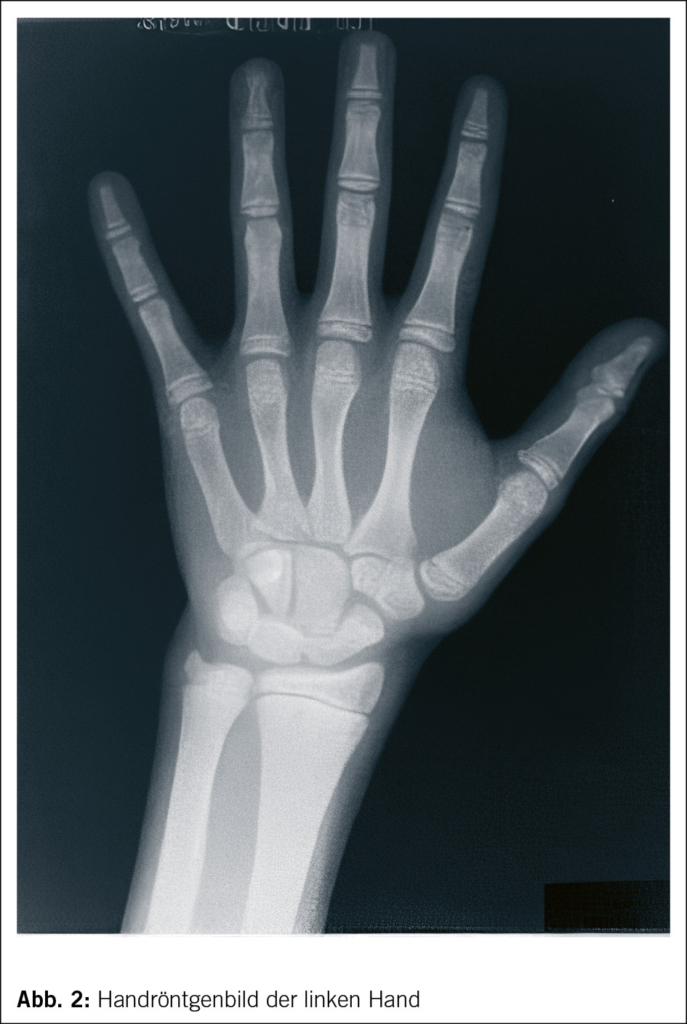

Bedeutung des Handröntgenbildes

Zu jeder Wachstumsabklärung gehört ein Handröntgenbild der linken Hand, damit das Knochenalter bestimmt werden kann (Abb. 2). Die Knochenreifung (man spricht auch vom «Knochenalter») ist ein gutes Mass für das biologische Alter. Aufgrund des Handröntgenbildes können erfahrene Ärzte berechnen, wann ungefähr die Pubertätsentwicklung beginnen wird, das heisst, ob sie früh oder spät einsetzen wird. Daraus lässt sich ableiten, wie gross ein Kind letztlich als Erwachsener sein wird.

Die Knochenreifung verläuft normalerweise, zumindest ab etwa dem 5. Lebensjahr, ziemlich linear. Eine Verzögerung oder eine Beschleunigung der Knochenreifung bleibt während Jahren bestehen. Die Extrapolation in die Zukunft der Beziehung des Knochenalters zum chronologischen Alter ist die rationale Basis für Wachstumsprognosen. Wenn das biologische Alter dem chronologischen Alter vorausgeht, beginnt die Pubertät früher und das Kind ist früher ausgewachsen (konstitutionelle Beschleunigung oder Frühentwickler). Umgekehrt kann die Knochenreifung in Bezug auf das chronologische Alter verzögert verlaufen. Dann beginnt die Pubertät verspätet, das Kind wächst länger und ist erst später ausgewachsen als der Durchschnitt der Gleichaltrigen – und zwar in der Regel ohne irgendeine krankhafte Störung (Konstitutionelle Verzögerung bzw. Spätentwickler).

Fast alle behandelbaren Wachstumsstörungen, nämlich Zöliakie, Hypothyreose und Wachstumshormonmangel, gehen mit einer Verzögerung des Knochenalters einher. Bei Kindern, die gastroenterologisch völlig beschwerdefrei sind, wird die Zöliakie oft nur aufgrund des verlangsamten Wachstums oder eines verzögerten Pubertätseintritts diagnostiziert.

Der Wachstumshormonmangel ist eine komplizierte Diagnose, die auf mehreren Säulen steht. Neben der kleinen Körpergrösse muss eine unzureichende Wachstumsgeschwindigkeit dokumentiert sein. In der Regel fällt die Körpergrösse unter die dritte Perzentile, wenn die Wachstumsgeschwindigkeit unterhalb der 25. Perzentile liegt. Ist das Knochenalter um über 1 Jahr verzögert und das IGF1 (als Marker für die Wachstumshormonaktivität) erniedrigt, also unterhalb von –1 SD, ist die Durchführung von Wachstumshormon-Stimulationstests zu prüfen. Diese stellen zusammen mit der typischen Klinik den Goldstandard für die Diagnose des Wachstumshormonmangels dar. In der Zeit unmittelbar vor der Pubertät sollte ein sogenanntes Priming mit Sexualhormonen (Testosteron oder Estradiol) vor dem Test durchgeführt werden (Abb. 3).